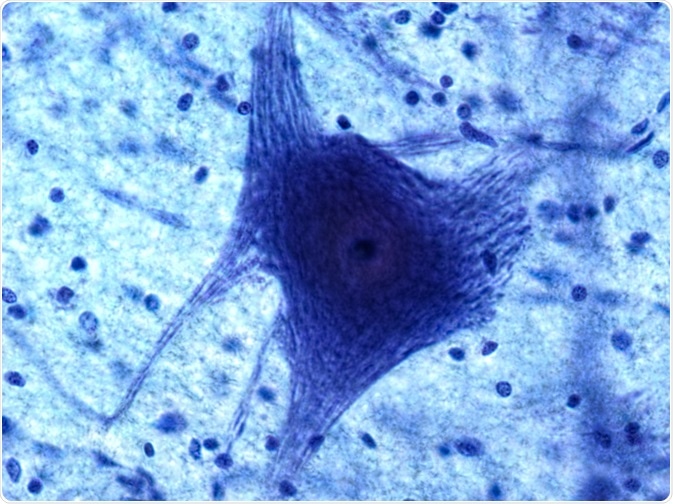

Neuron and Glia

Image Credit: Christopher Meade/Shutterstock.com